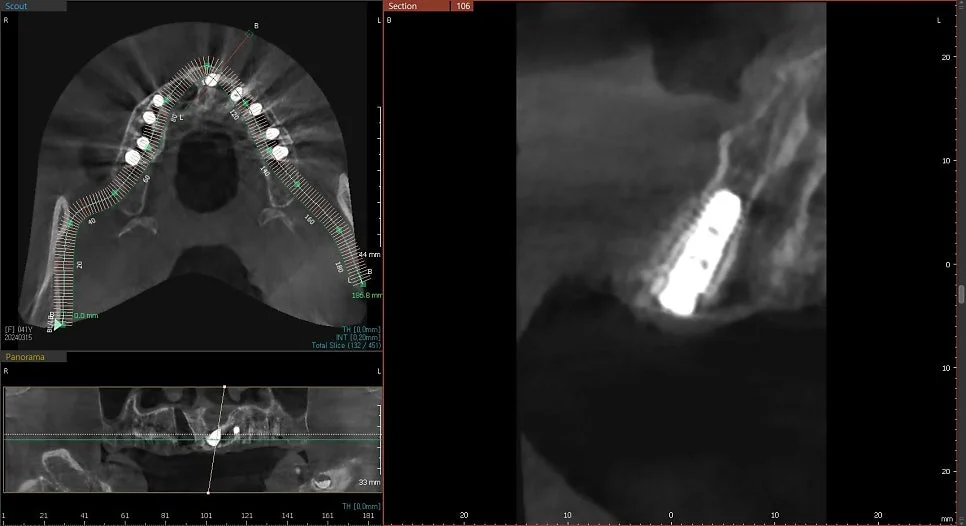

CBCT 단면 – 각 임플란트 개별 검증

CT 상에서 하얀색인 임플란트가 1. 온전히 뼈 안에 잠기게(1~2mm 깊게) 그리고 2. 가급적이면 입천장 쪽으로 식립되었다면 잘 심긴 임플란트입니다. (입술 쪽 뼈는 쉽게 흡수됩니다ㅜ)